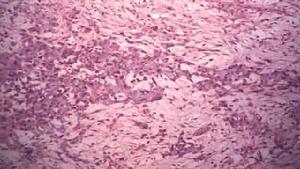

經典型主要表現為真皮及皮下組織內呈結節狀的腫瘤團塊,瘤體由上皮樣細胞和梭形細胞交織而成,周邊細胞可呈柵狀排列,腫瘤細胞體積較大,可為多邊形上皮樣細胞,核大深染,有異形性,胞質豐富,嗜伊紅深染,另一類為梭形細胞,瘤體內可有片狀壞死,間質有明顯纖維結締組織,可有不同程度的炎性細胞浸潤。近端型上皮樣肉瘤腫瘤細胞主要由上皮樣細胞構成,細胞體積較大,異形明顯,核呈空泡狀,常有橫紋肌樣細胞的特徵,可見腫瘤性壞死。經典型和近端型兩型腫瘤免疫組化表現相似,上皮樣肉瘤的腫瘤細胞CK和vimentin 反應呈陽性,EMA 呈陽性。2.影像學檢查